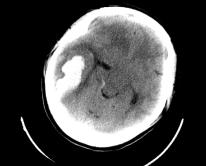

时间要回到去年4月,王女士(化名)从萧山转院到邵逸夫医院庆春院区急诊,送来的时候,人已经昏迷不醒,头颅CT诊断颅内出血,也就是脑中风。

王峰医生描述,女患者长相清秀,身高1米6,身材不是很胖,年纪也很轻,照理来说不是中风的高危人群。当时,一系列检查之后诊断明确,颅内出血30ml左右,情况紧急,由神经外科立即为她做了开颅手术,清除血肿。

患者右侧顶枕叶脑出血